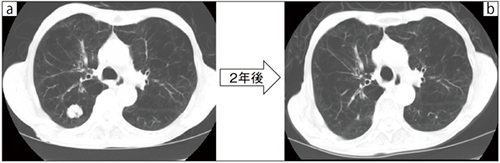

図2 代表的症例の治療経過

a:右肺下葉に20mm大の結節を認める。

b:結節は縮小し,肺臓炎は認めない。